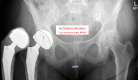

Background: Metal-on-Metal (MoM) total hip arthroplasties (THA) are associated with pseudotumor formation and high revision rates. This prospective study analysed the clinical and wear analyses of 9 large Metal-on-Metal (MoM) total hip arthroplasties (THA) to understand the underlying mechanisms of failure. The MoM bearings were revised for multiple reasons; the main reason was pseudotumor formation.

Materials and methods: From 2006 till 2010 the Reinier de Graaf Hospital implanted 160 large head M2a-Magnum™ (Biomet Inc. Warsaw, Indiana, USA) THAs in 150 patients. The first year, 9 bearings were revised and analysed at the Biomechanics Section, Hamburg University of Technology, Germany. We performed clinical (Harris Hip Score, radiographic analysis, blood cobalt and chromium) and wear analysis (implant, tissue and fluid) of the 9 bearings. Since this study did not fall under the scope of the Medical Research Involving Human Subjects Act in The Netherlands, no ethical approval was necessary. In this prospective study all patient details were anonymized by the corresponding author, all other authors were blinded during the research and wear analyses. Patients with bilateral MoM implants were excluded.

Results: The 9 bearings had a median (IQR) survival of 41.0 (25) months in situ. From these bearings, three showed no noticeable wear. The median (IQR) head wear volume was 3.2 (3.6) mm3 and maximum wear depth 0.02 (0.02) mm. For the cup the median (IQR) wear volume was 0.23 (0.3) mm3 with a maximum wear depth of 0.03 (0.05) mm.